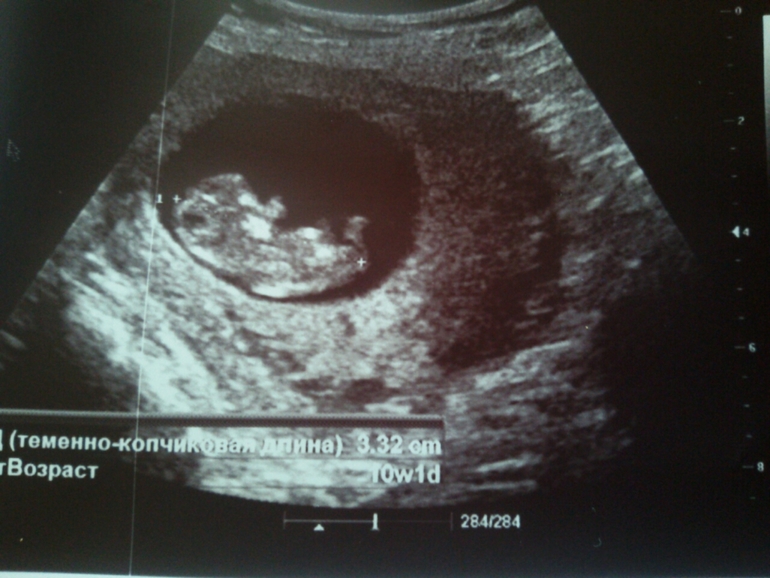

Вчера раскровилась... Тонус и все дела. Сегодня сделали внеплановое УЗИ. Первое, что сказала моя врач - "Живой!"

И это главное. Появилась отслоечка, на несколько неделек теперь закроют в больничку:) ну ничего! Отслойку мы переживем, главное, что живой! Всё остальное поправимо:)

За 6 дней мой Никитосик подрос на 8 миллиметров:) помахал нам ручками, ножками, покрутил головой, открывал ротик и пускал... Пузырики))))

Настраиваюсь на долгое пребывание в стационаре. Самый опасный срок у меня с 10 до 16 недель. В этот период происходили последние В и ЗБ.